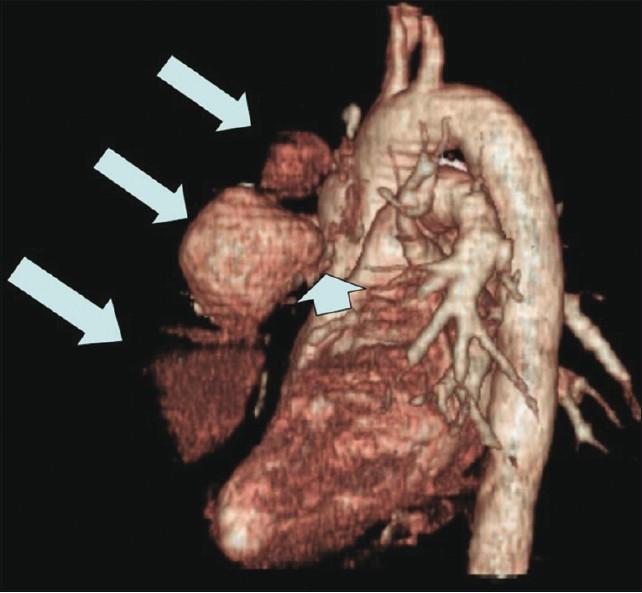

Pseudoaneurysm of ascending aorta is an infrequent but well-recognized and potentially fatal complication after cardiac surgeries. The complication can develop early, delayed or late, and the presentation is also varied. We are presenting here two cases of pseudoaneurysm of ascending aorta following cardiac surgery that were successfully managed by the transcatheter method. The first one occurred following coronary artery bypass surgery and the second one occurred following double-valve replacement surgery. The aortic openings of these aneurysms were occluded with 12 mm and 10 mm atrial septal occluders, respectively, with a good outcome. An immediate postprocedure angiogram showed no residual flow into the sac. Six months of follow-up of both cases also showed excellent results.

升主动脉假性动脉瘤是心脏手术后一种罕见但已被充分认识且可能致命的并发症。该并发症可早期、延迟或晚期发生,表现也各不相同。我们在此呈现两例心脏手术后升主动脉假性动脉瘤病例,均通过经导管方法成功治疗。第一例发生在冠状动脉旁路移植术后,第二例发生在双瓣膜置换术后。这些动脉瘤的主动脉开口分别用12毫米和10毫米的房间隔封堵器封堵,效果良好。术后即刻血管造影显示无血液残留进入瘤腔。两例患者术后6个月的随访结果也都非常理想。